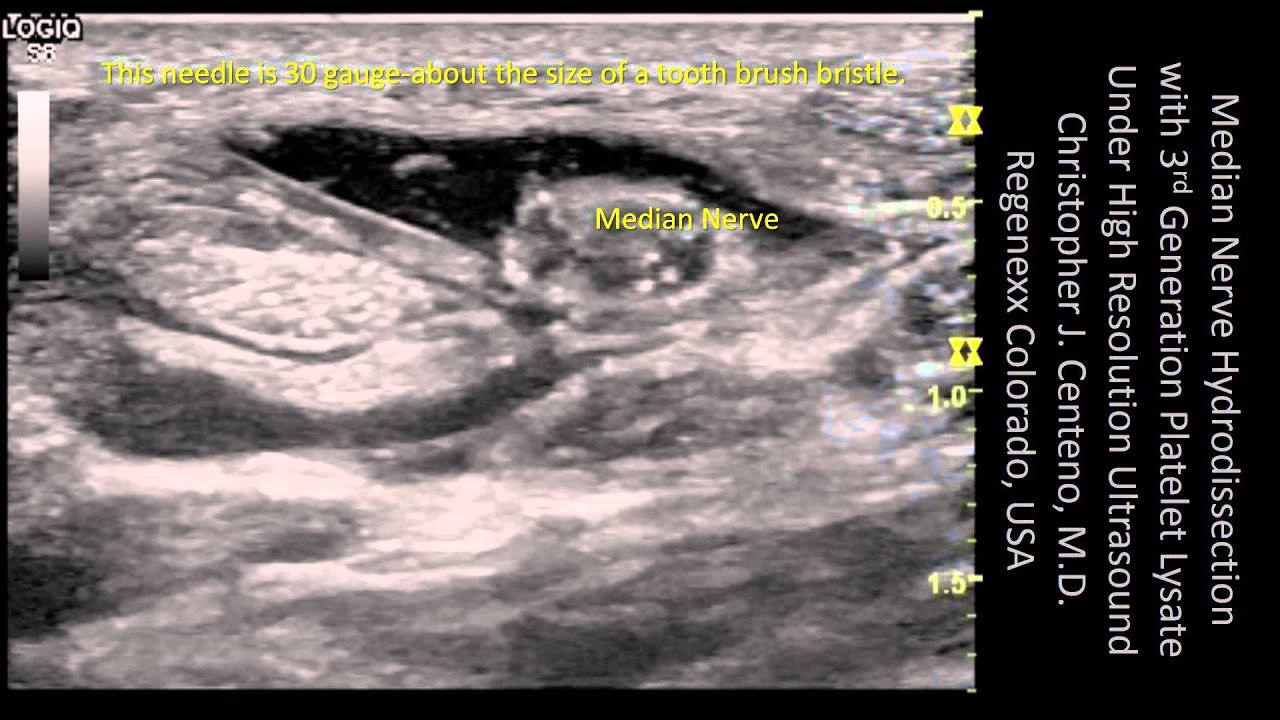

PRP, or platelet-rich plasma, can be a beneficial solution for treating mild arthritis in joints, ligament tears, or small tendons. We’ve found that Platelet Lysate has preferred characteristics for use around nerves. For this reason, it is used extensively in the spine, where we encounter irritated nerves due to disc bulges. It’s also a useful option for treating nerve-related issues like carpal tunnel syndrome, or other similar types of conditions. To see how Regenexx-PL injectate is used there, watch the video below, which shows a precision, ultrasound-guided, nerve hydrodissection.

Video: Precise Hydrodissection Using Ultrasound Guidance